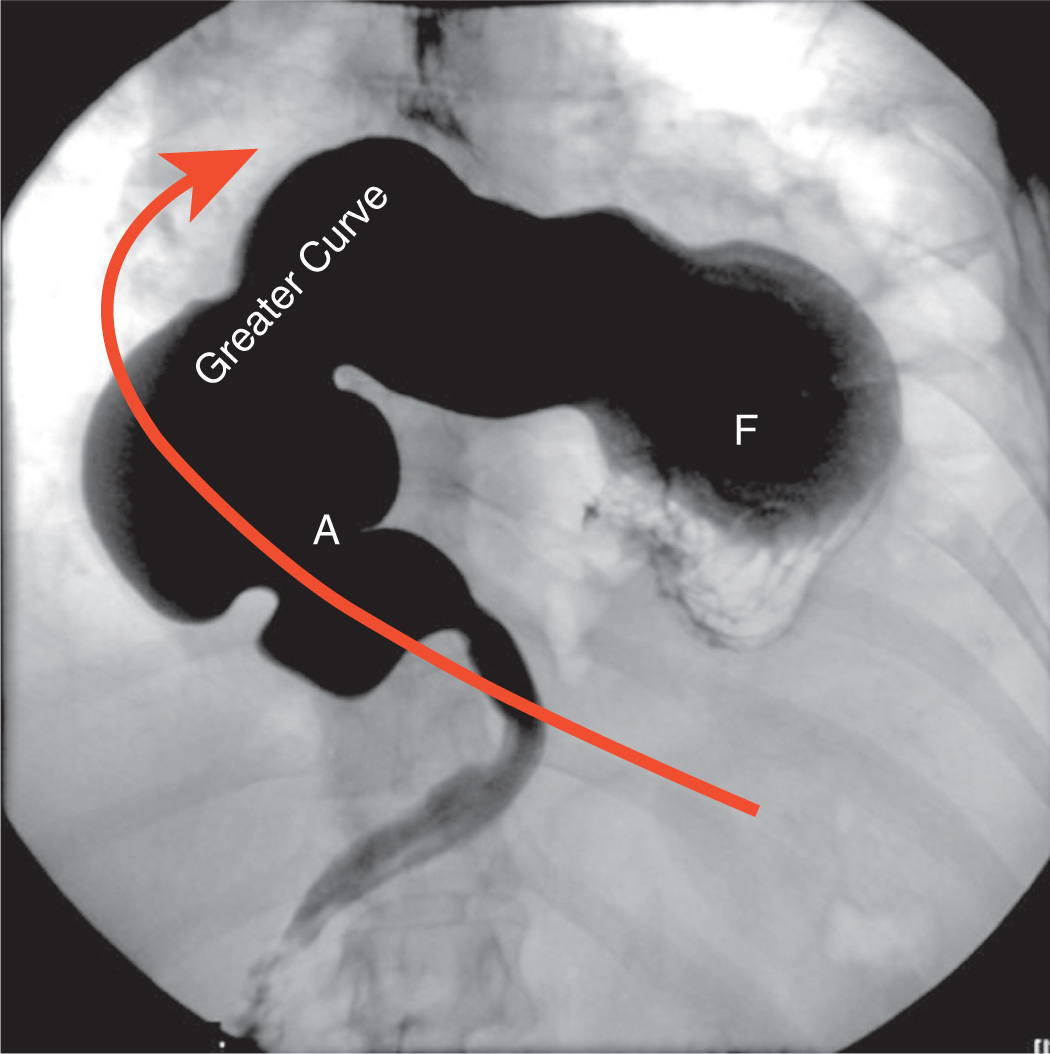

What is going on in this spot fluoroscopic film?

This is organoaxial volvulus of the stomach. It is most likely due to a large hiatal hernia into the chest (type IV hiatal hernia).

It produces an ‘upside-down’ apperance of the normal anatomy. These patients will typically present with epigatric/chest pain and vomiting.